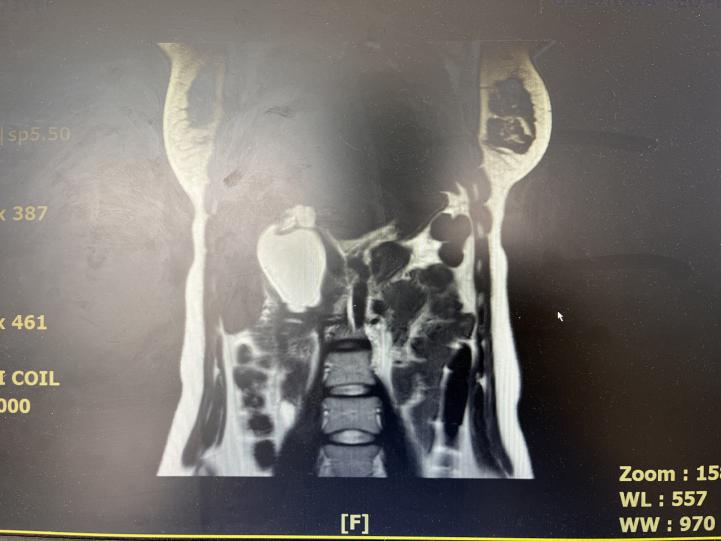

手术患者术后半年内每3个月、半年后每6个月复查血常规、肝功能、血清淀粉酶、肿瘤标志物)及腹部彩色多普勒超声、CT、MRI等影像学检查。综上所述,对于先天性胆总管囊肿,术前评估非常重要,腹部B超为首选,磁共振胰胆管造影为诊断金标准。因先天性胆总管囊肿存在较高的癌变率,一旦确诊为胆总管囊肿,应尽早行手术治疗。